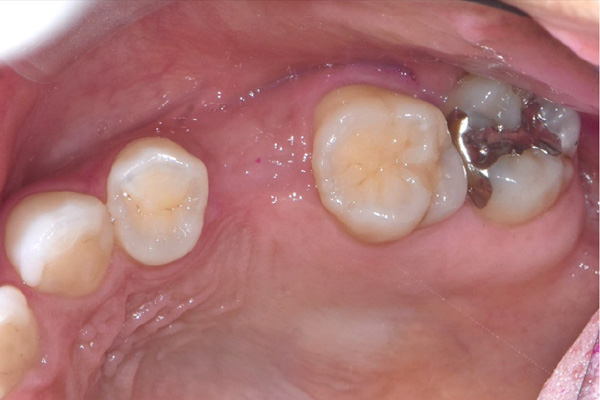

| 主訴 | 右下の歯がないのでインプラントをして欲しい |

| 治療期間 | 約6ヶ月 |

| 費用 | 600,000円 |

| 治療内容 | インプラント、骨造成、結合組織移植、セラミック修復 |

| 治療に伴うリスク | インプラント周囲炎 セラミックの破折、脱離 |